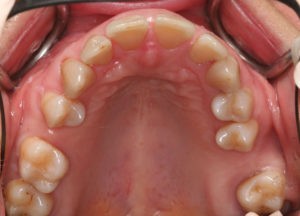

Для предварительной подготовки были привлечены пародонтолог и ортопед, поскольку отсутствие нескольких зубов, заболевание пародонта и дефекты твердых тканей зубов сопутствовали основной патологии. Проведены пародонтологические процедуры, вылечен кариес и его осложнения, изготовлены временные коронки для зубов с большим разрушением. На фото — временные коронки на боковых зубах.

Искривление окклюзионной кривой (плоскости смыкания зубов), возникшее в результате парадонтита, успешно удалось устранить, используя накусочные брекеты на верхних резцах и микроимплант, установленный во фронтальном участке нижней челюсти: